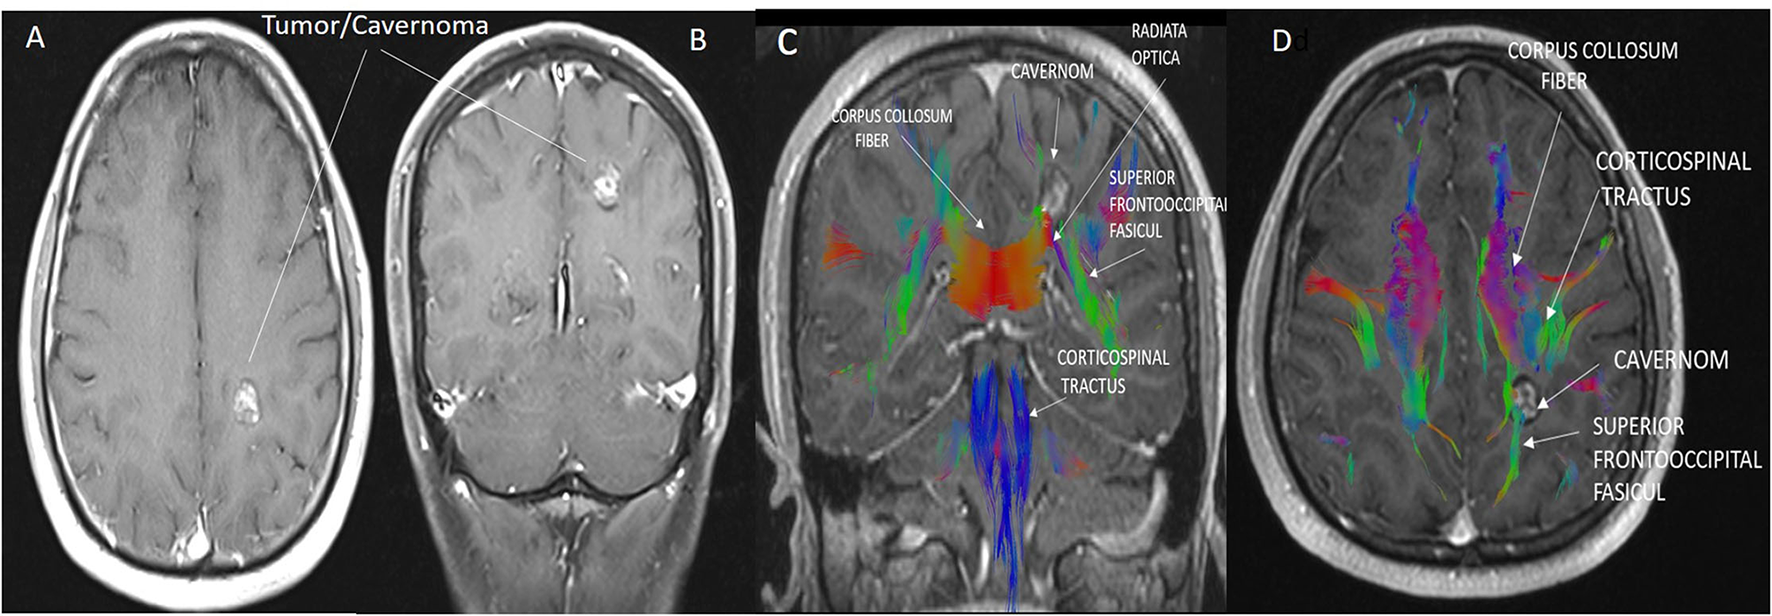

In MR tractography, the blue coding shows the corticospinal tract with a top-down (craniocaudal) course, the red coding for the transverse course in the corpus callosum and subcortical areas, and the green coding for the anteroposterior front-occipital tracts.

The borders of the preoperative brain tumor lesion (reward) were determined as the contrast-enhancing area in T1 contrast MRI imaging (19). Tracts with diffusion tensor imaging (DTI), arterial anatomy with contrast-enhanced MRI angiography (CE-MRA), and those with tumor tissue (20) superficial cortical vessels and dural sinuses are used in surgical planning with MRI venography (21) (Figure 2). DICOM images in the respective sequences were imported into the labeling program (labelme 4.6.0, https://github.com/wkentaro/labelme). Functional anatomical areas were marked and labeled by the radiology and neurosurgeon specialist (Figure 3). The pixel and voxel values of the anatomical point and the anatomical structure of the point were listed by labeling (22, 23). This gave us the advantage of trading in a cubic system with matrixes.

Figure 2. (A,B) Cavernoma appearance on axial (A) and coronal (B) contrast-enhanced T1 cranial MRI images. (C,D) The anatomical relationship of the corticospinal tract, superior fronto occipital fasciculus, and corpus callosum transverse fibers with the cavernoma is shown in sagittal and axial MRI tractography images. Due to the mass effect of the cavernoma, displacement of the superior fronto occipital fasciculus was observed.